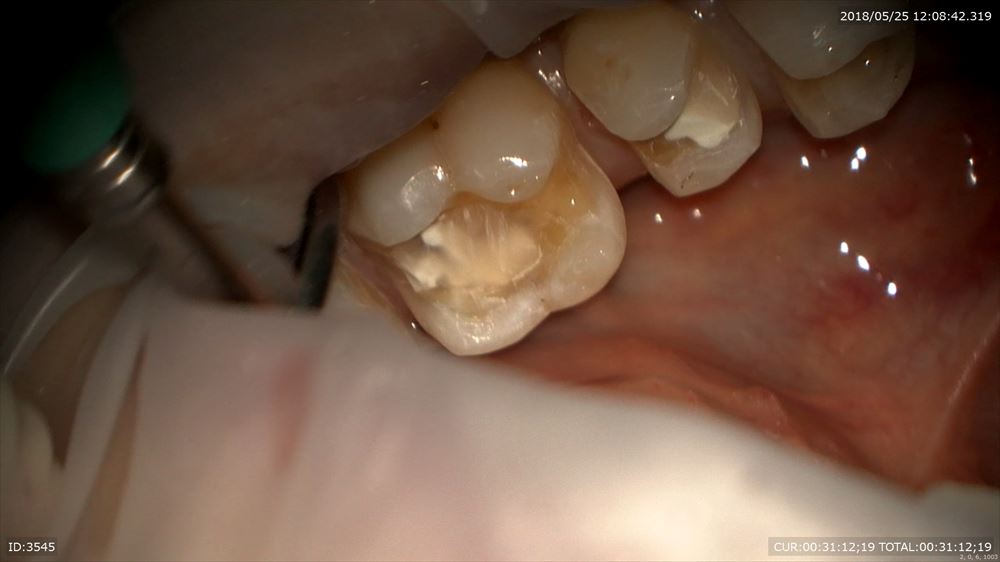

クラックの修復。

秋山勝彦先生にご指導のお蔭でこの様にマイクロスコープですべて直視下でできます。

6番の遠心見えます。

だから丁寧な形成が可能。両手が使えるから。

歯茎に1mmも触らずにできるから血もでません。無痛!!